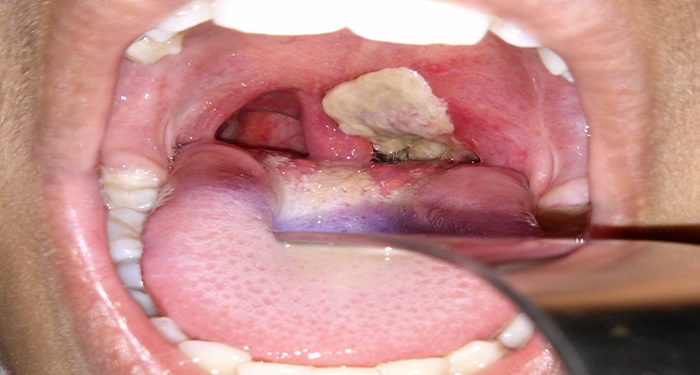

The Director General of Kano State Primary Healthcare Management Board, Dr. Muhammad Mahmud, has said that about 520 children are suspected to have lost their lives following the diphtheria outbreak in the state in 2023.

“There is data we generated through our digit surveillance and reporting system. This year, Kano reported about 8,700 suspected cases of diphtheria and 6,300 confirmed, with about 520 children suspected to have died of this illness.

Mahmud who described Diphtheria as a threat to child survival, health and the well-being of children, said UNICEF is collaborating with the government and other partners to respond to the emergency to save the lives of the children affected.